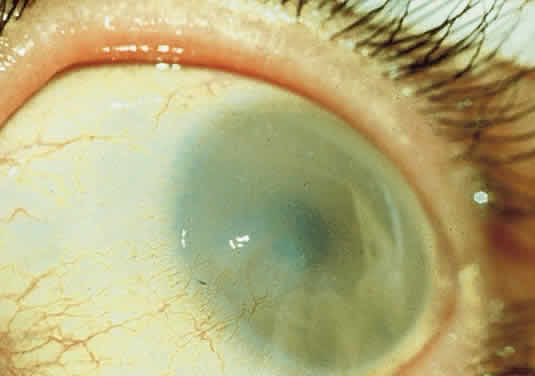

OCULAR FINDINGS. The outstanding clinical feature common to all three phenotypes is the corneal and conjunctival cystine crystal deposition (Figs. 3 and 4). Photophobia is often the only presenting visual symptom; this may be incapacitating and associated with blepharospasm.

Corneal deposits appear as a layer of homogeneously distributed, fusiform or needle-shaped, iridescent crystals situated in the stroma beneath the epithelium. In the infantile form, anterior crystal deposition begins early in life (between 6 and 15 months of age) and proceeds posteriorly as the patient ages; deposition advances more rapidly in the periphery. The anterior location of the crystals may be associated with recurrent erosions.33 The depth of the stromal deposition and the density of crystals is always greater peripherally than centrally. More and larger crystals occur in the superficial stroma. No visual impairment occurs at this early stage. By the age of 7 years, most patients have crystals, either within or on the endothelial surface34,35; markedly decreased corneal sensitivity is also present.36 The spherical contrast sensitivity function is significantly lower in infantile cystinosis than in age-matched controls.37

The conjunctiva has a ground-glass appearance. Polychromatic, polymorphic, rectangular, or rhomboidal crystals can be seen with the biomicroscope.

The uvea contains an abundance of polymorphous crystals. Clinically, these can be seen as glistening dots on the surface of the iris. Thickened iris stroma and posterior synechiae may occur; pupillary block glaucoma38 also has been reported. The entire uvea has polymorphic crystal deposition, most heavily in the choroid. The sclera also has crystal deposition.